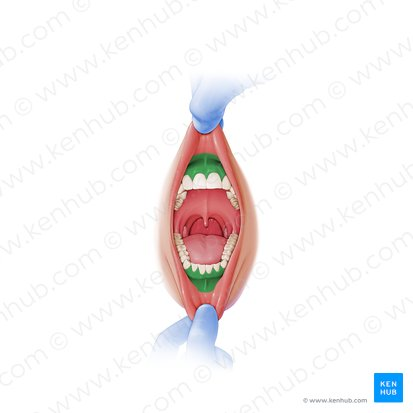

green highlight

Dorsum of tongue

blue box

Body of tongue

yellow box (referencing a section of the tongue)

Root of tongue

pink box

Papillae

Lingual frenulum

Openings of submandibular ducts